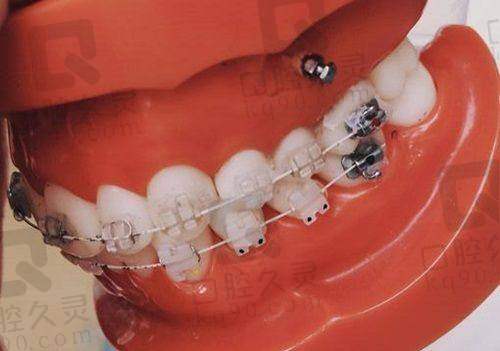

牙齿矫正也是医院的特色项目之一。医院拥有多种矫正方式,如传统金属矫正、陶瓷矫正、隐形矫正等。医生会根据患者的牙齿畸形程度和个人需求,制定更适合的矫正方案,帮助患者拥有整齐美观的牙齿。